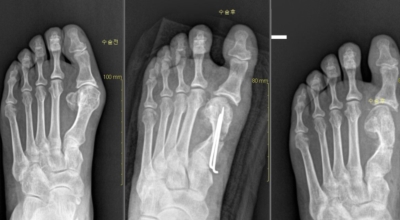

초기 단계에서는 건막류(두꺼운 혹)를 절제하는 건막류절제술을 시행해요. 돌출된 건막류를 절제해서 각을 교정하고 짧아진 근육 또는 연부조직을 늘려주는 비교적 간단한 수술입니다. 다른 발가락의 변형이 동반되거나 뼈의 과잉성장이 심하면 뼈를 깎고 방향을 돌린 뒤 발가락이 똑바로 펴지도록 철사로 고정시키는 등 교정절골술을 시행해요. 양 발이 모두 변형된 경우 대부분이 한 번에 한쪽만 수술해요.